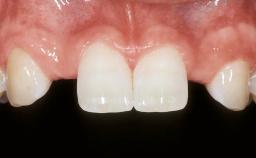

| Case Type | Single-Tooth Space |

| Jaw | Maxilla |

| Area | Anterior |

| # of Teeth | 1 |